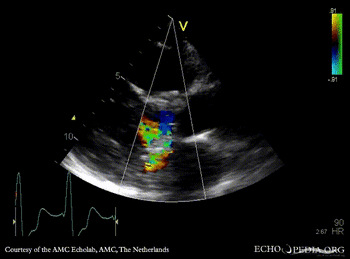

Four prosthetic valves

A4CH: mitral valve prosthesis and tricuspid valve prosthesis A5CH with Color Doppler